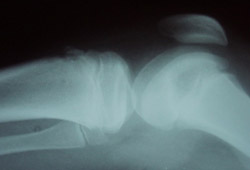

- prominence of the tibial tubercle